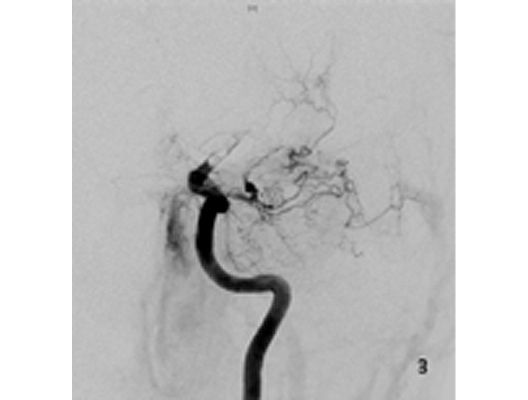

Das Beispiel zeigt die angiographischen Bilder einer Patientin, bei der es zu einer Sehstörung gekommen war. Die Ursache war ein großes Aneurysma der Halsschlagader an der Schädelbasis (Bild 1). Bild 2 zeigt die Lage des Aneurysmas hinter dem Auge. Durch den Druck des Aneurysmas auf den Sehnerv war es zu der Sehstörung gekommen. Die Patientin wurde mit einer speziellen Gefäßprothese versorgt, welche über eine Punktion der Leistenarterie in die Halsschlagader eingesetzt wurde (Bild 3). Bei der Kontrolle nach 6 Monaten zeigte sich ein vollständiger Verschluss des Aneurysmas (Bild 4). Die Sehstörung hatte sich vollständig zurückgebildet.